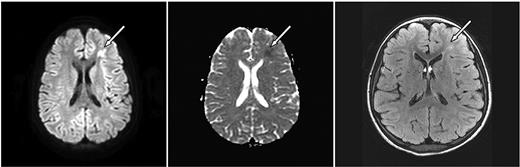

ASCIE were identified by DWI in 4 (18.2%) of 22 children with SCD and 2 (6.7%) of 30 without SCD (P = .382, Table 1). All had areas of restricted diffusion on DWI with corresponding areas of decreased signal on ADC map. There were corresponding abnormalities on the initial FLAIR images in 4 of 6. DWI lesions were subcortical or in the deep white matter (Figures 1–2). One patient had deep white matter DWI lesions and a lesion in the splenium of the corpus callosum without history of seizure. Two of the 6 patients had multiple DWI lesions, 4 had solitary lesions.

Axial MRI images of case 3. A 10-year-old girl with SCD and parvovirus infection with hgb = 2.9 g/dL showing (left, arrow) an area of restricted diffusion on DWI images with an ACD correlate (middle). Follow-up FLAIR MRI 7 months later (right) shows a lesion corresponding to the affected area on the DWI.

Follow-up MRI studies (Figures 1–2) were obtained 2.5 to 7 months later for other clinical indications for 4 of 6 of the patients with ASCIE; 3 had lesions on FLAIR images consistent with SCI in locations corresponding to the ASCIE on the initial study MRI (Table 1) and thus meet the definition of acute SCI. All 3 had SCD. Notably, the patient without a corresponding lesion on follow-up imaging also had no FLAIR correlate on the initial study MRI. This patient did not have SCD. We believe this to be a transient, reversible ASCIE.7 Magnetic resonance angiography (MRA) was not part of our study protocol but was obtained for the clinically indicated follow-up studies for 4 of 6 of the patients with ACSIE and was normal in 3, with 1 patient demonstrating subtle vascular irregularities in the internal carotid artery and middle cerebral artery ipsilateral to the ASCIE (Table 1).